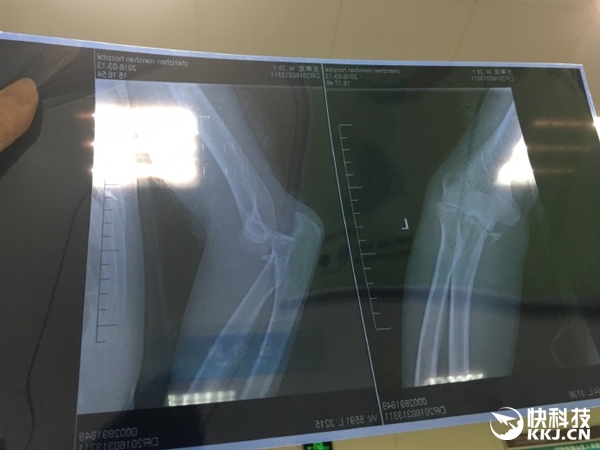

日前,微博網友@王奔宏 發帖稱,人生的第一次住院獻給了小米平衡車”,并展示了自己的住院證明和骨折拍片。

剛剛,@王奔宏 再次發微博稱:“為了避免給小米和納恩博產生不必要的負面影響,這里澄清一下事故過程,當時的確下了點小雨,路面有些濕滑,但我車速并不快,平衡車行駛到瓷磚地面后其中一個輪子突然打滑,于是我便失去平衡重摔在地面上,因為左手下意識里進行了支撐,所以致使左側尺骨冠突粉碎性骨折。”